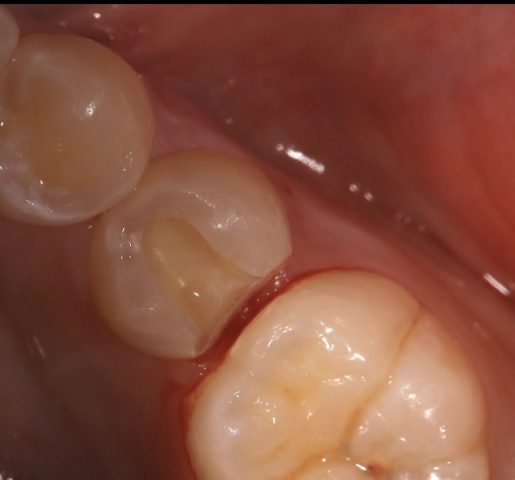

セラミック治療審美歯科

セラミックインレーの審美補綴治療

Before

After

| 診断名 | セラミックインレー審美補綴治療 |

|---|---|

| 年齢・性別 | 50代・女性 |

| 治療期間・回数 | 2週間~3週間/2回 |

| 治療方法 | セラミックインレーによる審美補綴治療 |

| 費用 | 55,000円(税込み) |

| デメリット・注意点 | 保険が適用できないため自費診療になる。 セラミックスインレー・クラウンに強い力がかかると割れてしまう恐れがあるため、歯ぎしりや食いしばりが癖になっている患者様にはおすすめできない場合がある。 |